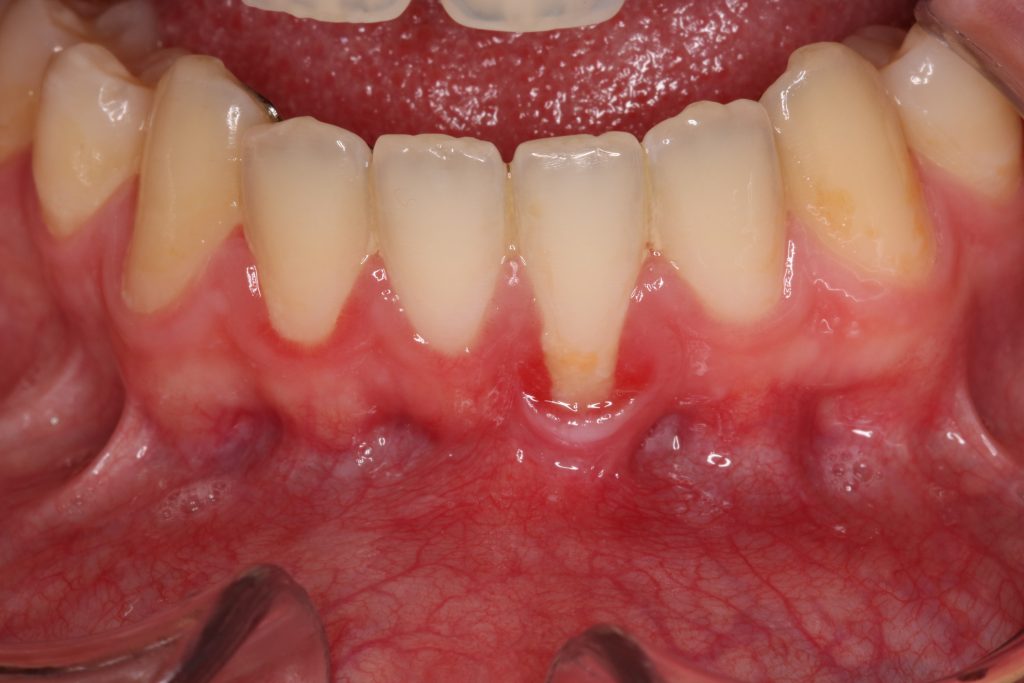

Ill. 1 : Guérison normale après une greffe de gencive libre. Noter la couleur blanchâtre que le patient pourrait interpréter comme une perte de greffon. (Photo reproduite avec l'aimable autorisation du Dr Peter Halford) Ill. 2 : Guérison normale 7 jours après une greffe de gencive libre. Les zones blanchâtres indiquent un décollement de.